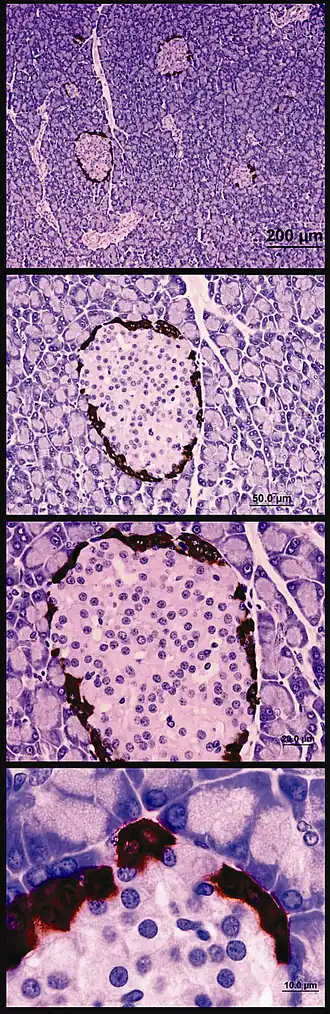

Alfacellen zijn ongeveer 10 μm groot[3] met een oppervlak van 60 μm2.[4] Ze slaan glucagon op granulen in secretoire vesikels die doorgaans onder een electronenmicroscoop een elektronendichte kern en een grijsachtige buitenrand hebben.[1] Als secretiecel heeft de alfacel een aanzienlijk golgicomplex en een groot aantal mitochondriën. De celkern vertoont compact heterochromatine aan de periferie en een geplooid celmembraan.

Aangenomen wordt dat alfacellen ongeveer 20% van de endocriene cellen in de alvleesklier uitmaken. Alfacellen worden meestal aangetroffen aan de dorsale zijde van de alvleesklier en zeer zelden aan de ventrale zijde.[1]